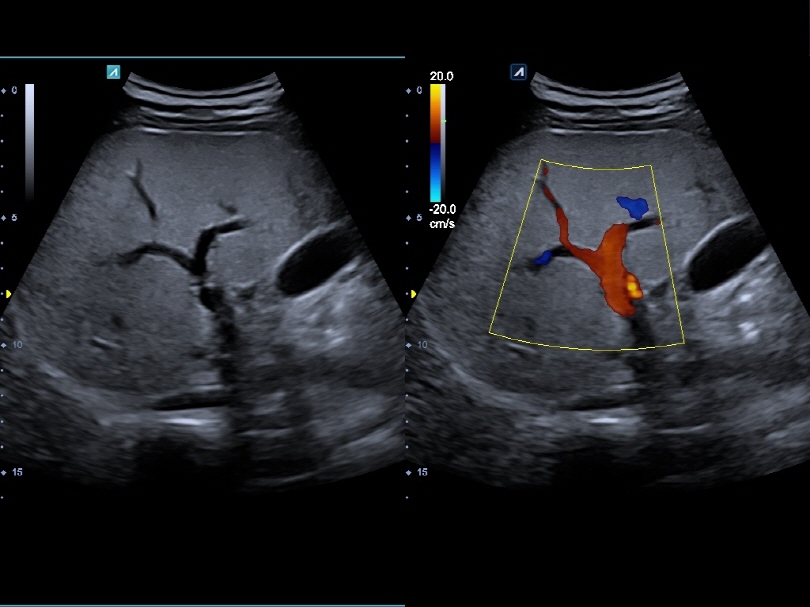

VC1-6T

Volume Convex (1-6MHz)

Application:

Abdomen, OB, GYN, EM